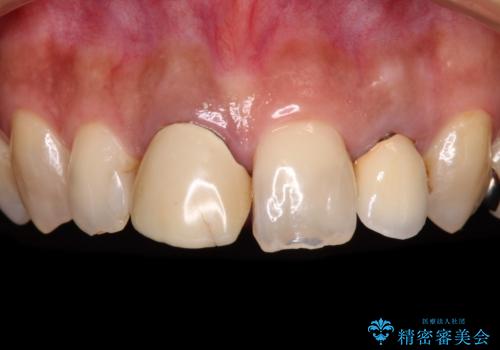

[ 歯が小さい ] 根管治療を伴う矮小歯治療

![[ 歯が小さい ] 根管治療を伴う矮小歯治療の症例 治療前](https://seimitsushinbi.jp/wp/wp-content/uploads/2021/09/c31c85cea60404f69948fd7103e8c7ca-500x350.jpg?v=1632883039)

![[ 歯が小さい ] 根管治療を伴う矮小歯治療の症例 治療後](https://seimitsushinbi.jp/wp/wp-content/uploads/2021/09/80796f663a2a5f8bf47550dede73495e-500x350.jpg?v=1632882140)